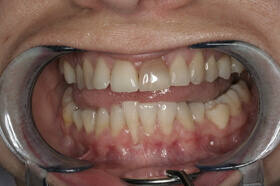

Agresszív fogágybetegség miatt kialakult frontfog elmozdulás – elülső nézet

Agresszív fogágybetegség miatt kialakult frontfog elmozdulás – oldalnézet